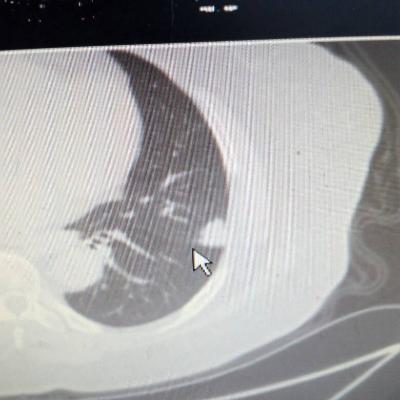

主诉:反酸、烧心5年,加重1年。 病史:患者5年前饮酒出现反酸烧心,并嗳气症状,剑突下烧灼感,饮酒及平卧后加重,无恶心呕吐,无腹痛腹泻,无吞咽困难,服用“达喜”后症状可缓解,易反复发作。3天前我科门诊示:胃镜反流性食管炎(LA-B),现为进一步诊治入院。

1.胃食管反流病 1.1反流性食管炎LA-B 2.食管裂孔疝 处理:患者诊断明确,行腹腔镜下食管裂孔疝修补术+胃底折叠术。

患者术后一周出院,反酸、烧心、嗳气症状明显缓解,无吞咽不畅等症状。 讨论:对于诊断有食管裂孔疝病人的胃食管反流病,且用药有一定疗效,建议行手术治疗,行腹腔镜下食管裂孔疝修补术,修补了膈裂孔,同时行胃底折叠术,加紧了贲门括约肌压力,共同形成抗“反流瓣”。